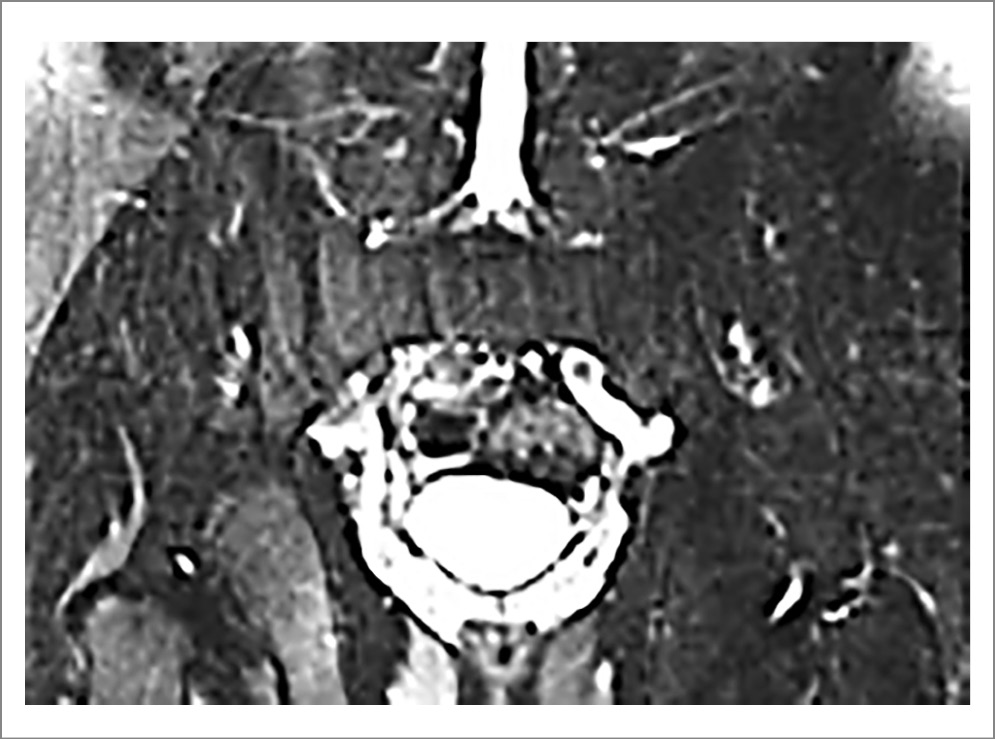

- Должен быть выявлен отек/воспаление костного мозга (остеит) – зоны гиперинтенсивного сигнала в режиме STIR или Т2 FatSat типичной локализации (субхондральные области КПС), имеющие визуализационные признаки, характерные для аксСпА (рис. 10).

- Зоны отека должны быть множественными или обнаруживаться на многих изображениях (срезах, последовательностях и плоскостях). Необходимо, чтобы зона отека была достаточно большой, не могла быть объяснена артефактами и другими причинами, которые способны индуцировать подобные изменения. Мелкие, отдельно расположенные (солитарные) очаги отека костного мозга должны интерпретироваться с осторожностью. Не принимается во внимание зона отека, расположенная исключительно в вентральной части сустава. Отек костного мозга в связочной области сустава не учитывается. Количество срезов МРТ, на которых выявляется отек, существенного значения не имеет.

- Воспаление других структур КПС (энтезит, капсулит), а также усиление сигнала от полости сустава (синовит), обнаружение жидкости в полости сустава и воспаление в месте эрозий имеют лишь подтверждающее значение и учитываются только в тех случаях, когда отек костного мозга выявляется неотчетливо.

- Наличие только структурных изменений КПС: жировая трансформация костного мозга; эрозии; жировая трансформация в полости эрозии, феномен «засыпки» (backfill); остеофиброз; анкилоз и костный выступ (bone bud) – не соответствует понятию «активного» сакроилиита по данным МРТ.

Рис. 10. Пациент Б., диагноз АС. МРТ КПС (коронарная проекция, режим Т2 FatSat): множественные зоны отека костного мозга (указаны стрелками) в основном в субхондральных областях. Изменения соответствуют критериям «активного» сакроилиита по классификации ASAS [22].